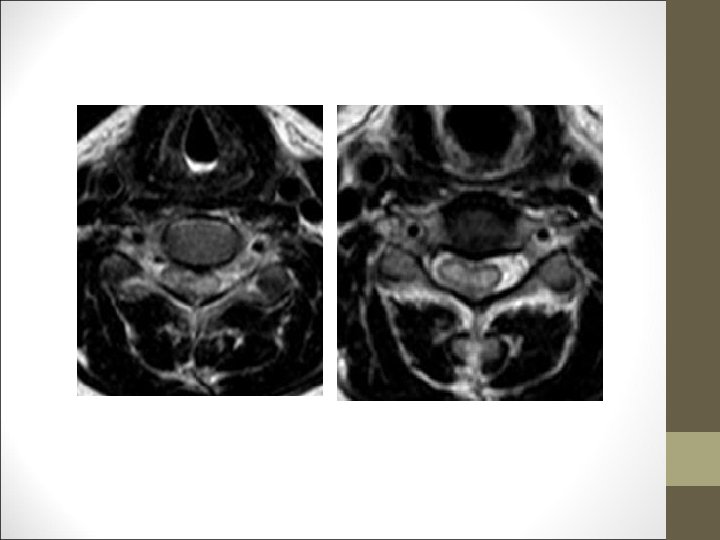

TC Desplazamientos de fragmentos óseos ¿Algo mas? FACULTAD DE MEDICINA DEPARTAMENTO DE CIRUGÍA NEUROCIRUGÍA RM Desplazamientos discales y lesiones ligamentosa